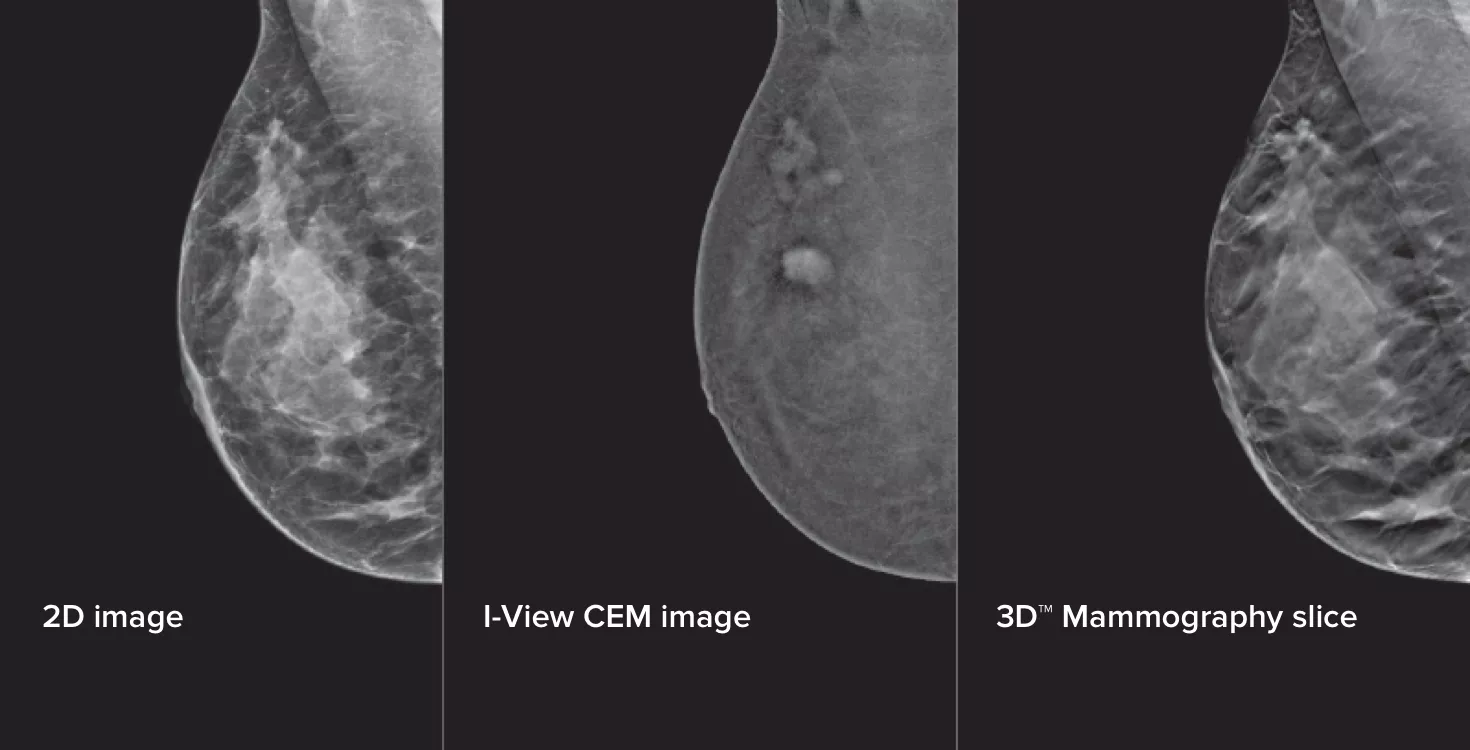

Contrast Enhanced Mammography (CEM), the imaging of a breast using iodinated contrast to reveal areas of increased blood supply within the breast, can help enhance suspicious lesions. The I-View software can combine the power of CEM with 2D and tomosynthesis images, all under one compression, providing anatomical and functional imaging in one exam.1

This software captures both anatomical and functional information in a single exam by leveraging our ability to provide 2D, contrast and tomosynthesis images in just one compression.1